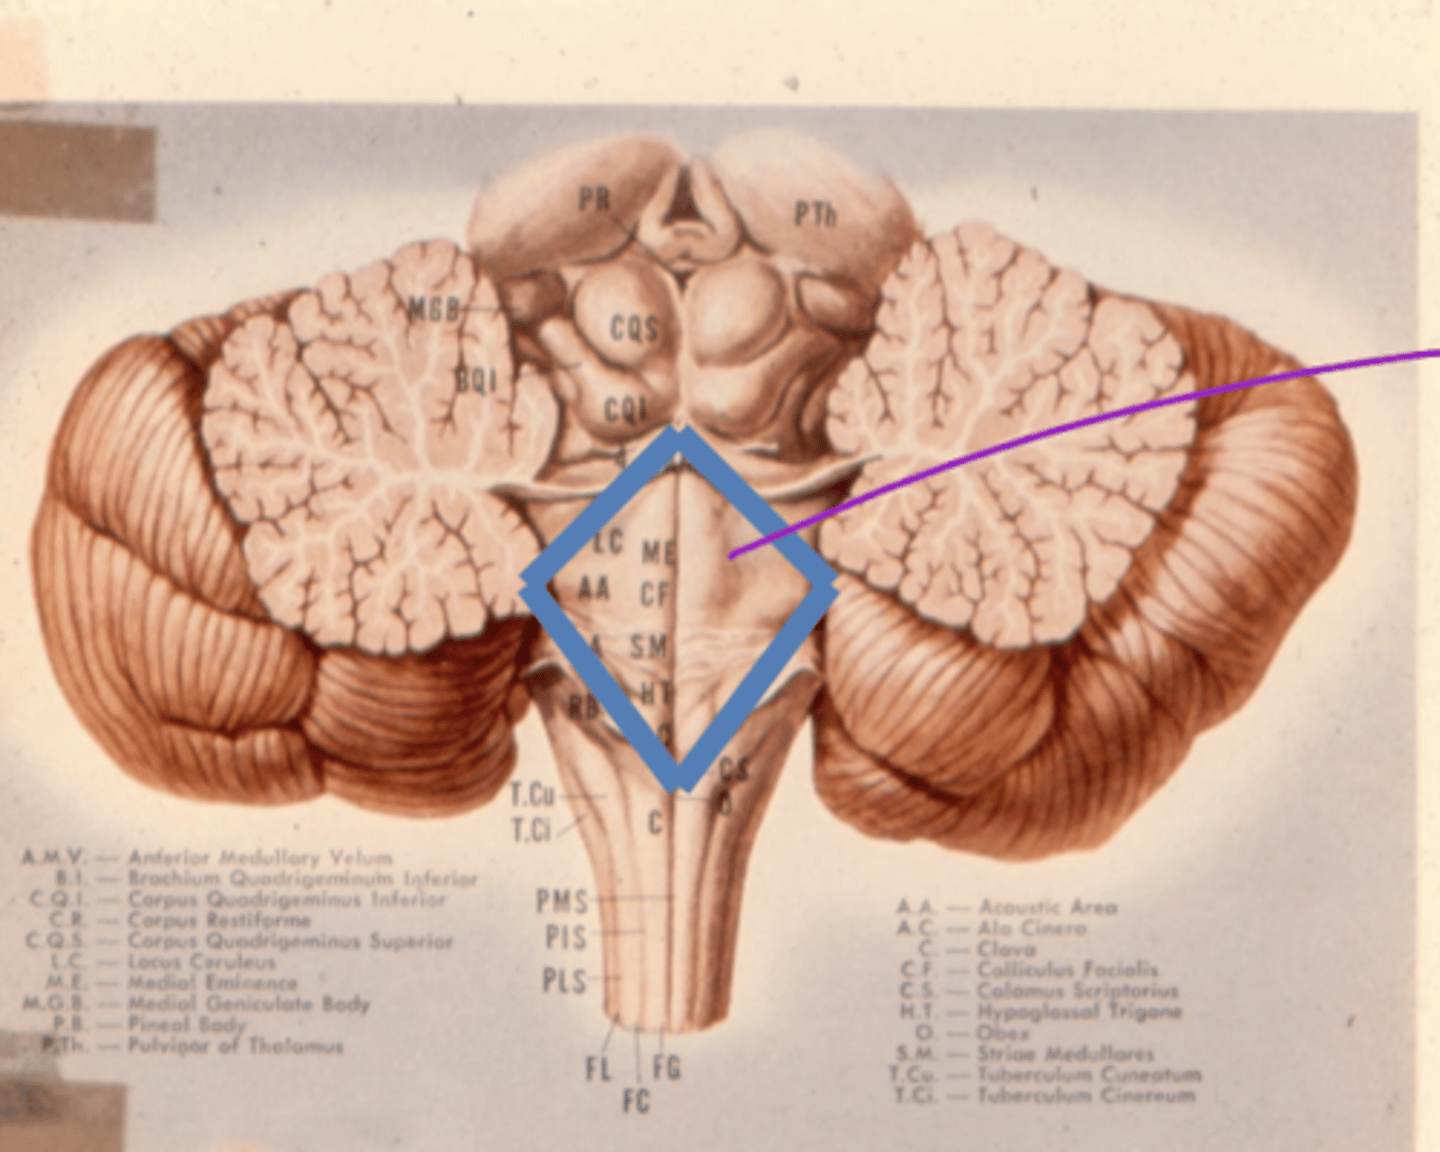

What is the floor of the 4th ventricle?

tegmentum pons

image -- green

What is the superior medullary velum?

membrane that forms the superior portion of the 4th ventricle roof

image -- 7

What is the inferior medullary velum?

membrane that forms the inferior portion of the 4th ventricle roof

image -- 1

What are the facial colliculi?

bumps (hills) coming out from dorsal pontomedullary junction into the 4th ventricle -- CN VII SVE fibers create this space when they wrap around the abducens nucleus

What is the rhombencephalon?

floor of 4th ventricle (for the sake of our class)

dorsal aspect of tegmentum of pons